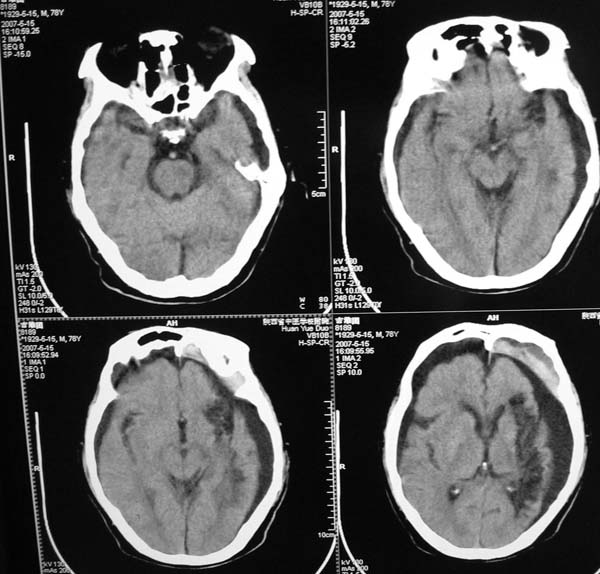

以下是引用star--868在2007-6-15 20:54:00的发言:[br]1.左侧额颞顶部亚急性硬膜下血肿并继续出血 双侧额颞顶部硬膜下积液;[br]2.左颞枕叶、左基底节区脑软化-左侧大脑中动脉栓塞;[br]双侧额颞顶部硬膜下积液应和治疗期间应用高渗脱水剂相鉴别:停用甘露醇后硬膜下积液会逐渐吸收减少,而单纯硬膜下积液无此改变和/或逐渐增多。

以下是引用狙击手在2007-6-15 21:15:00的发言:[br]软化灶就不必说了,主要是混和性血肿的渐变过程。

以下是引用老爱克斯新网客在2007-6-15 20:40:00的发言:[br]1左侧颞叶软化灶,2双侧硬膜下水瘤,3左册硬膜下血肿(多次少量出血),

以下是引用还珠格格在2007-6-16 7:07:00的发言:[br]支持.左侧额颞顶部亚急性硬膜下血肿并继续出血 双侧额颞顶部硬膜下积液;[br]2.左颞枕叶、左基底节区脑软化-左侧大脑中动脉栓塞;